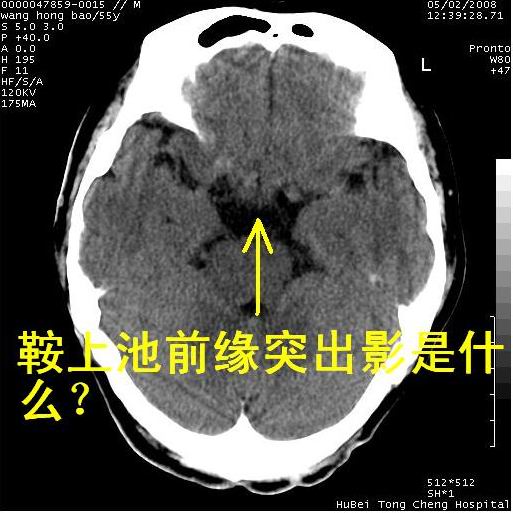

以下是引用qiushi在2008-5-4 10:10:00的发言:[br]鞍上池前缘突出影为双侧额叶直回;箭头所指为双侧正常之人字缝.[br]桥前池区可疑表皮样囊肿或蛛网膜囊肿,必要时mri